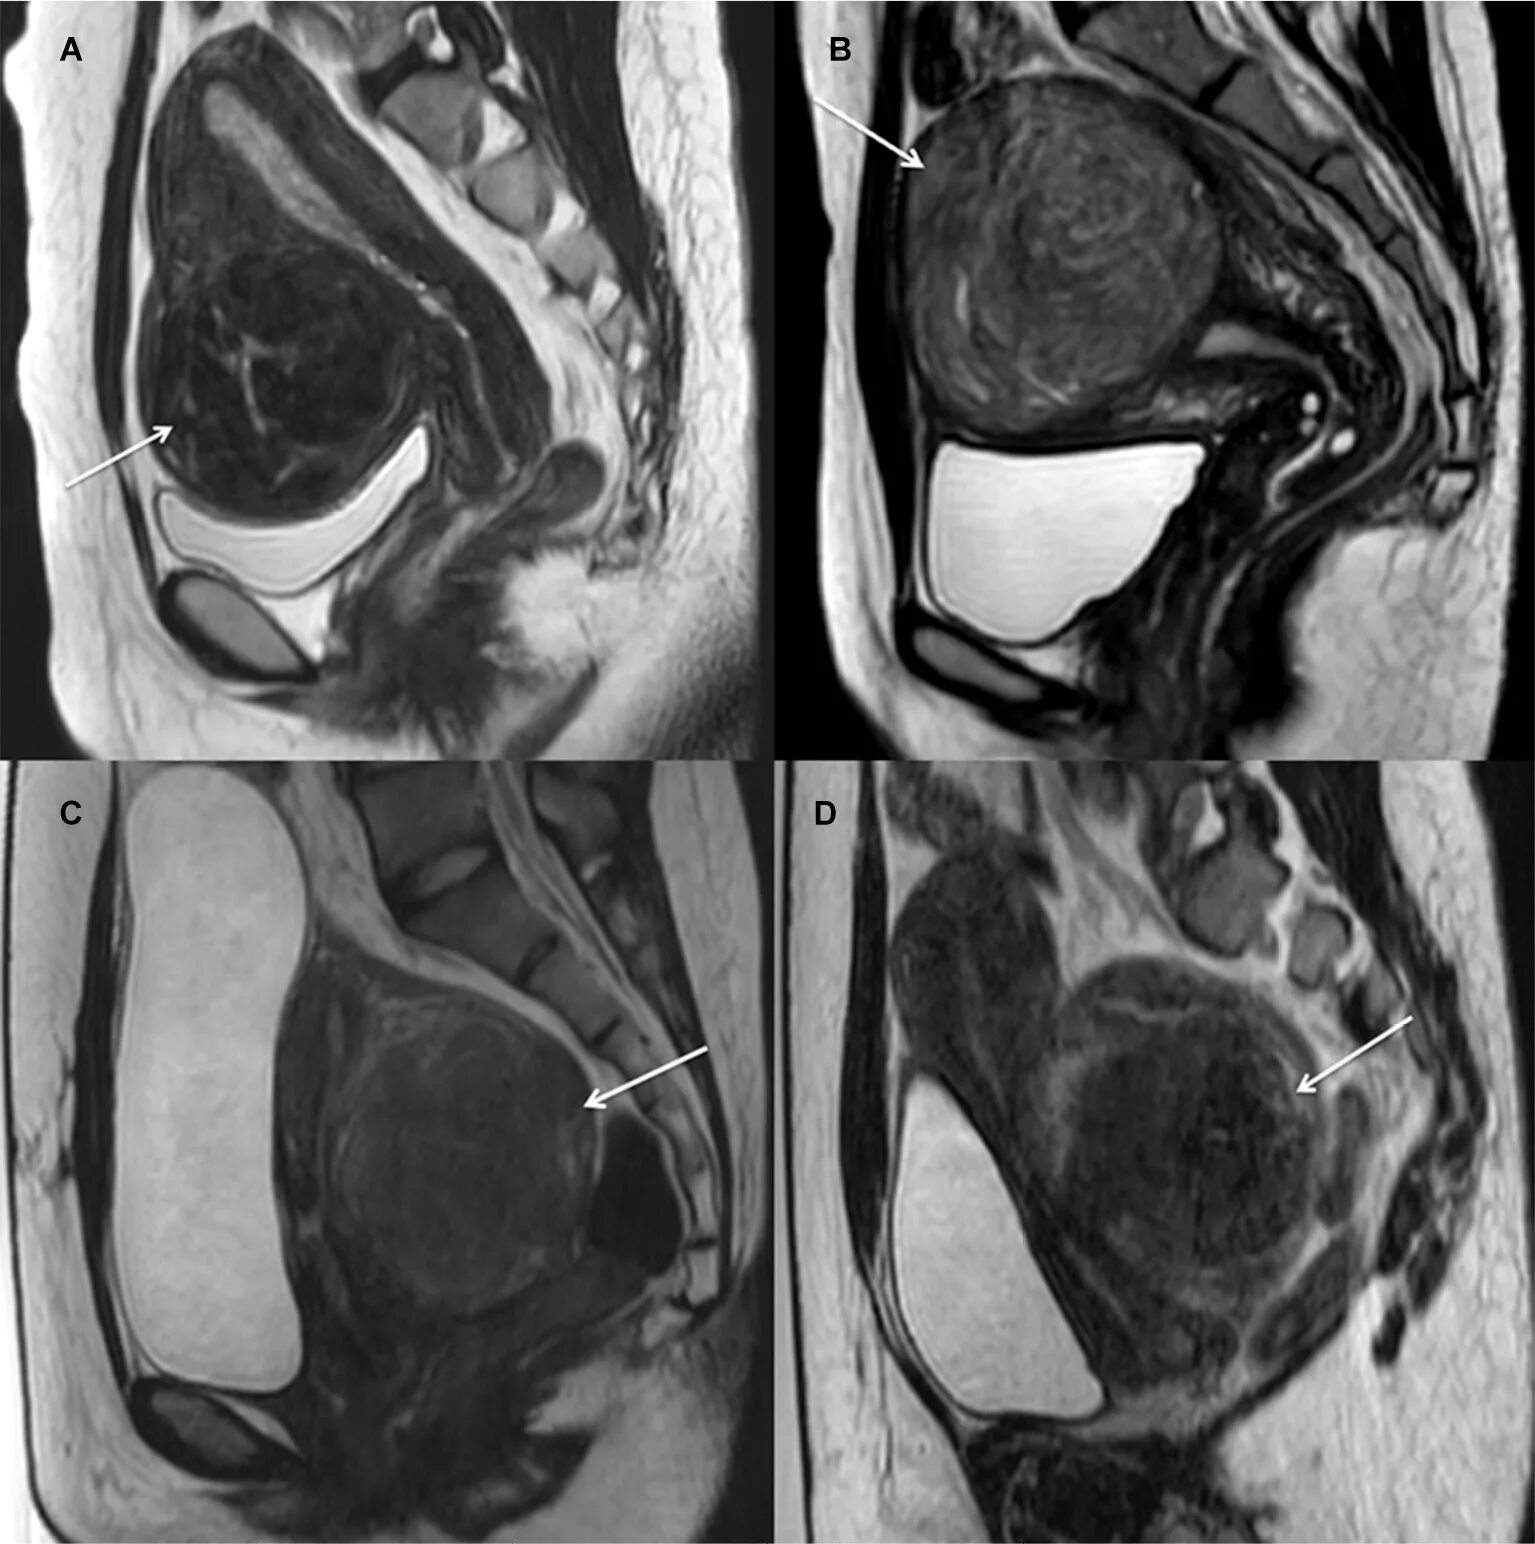

Саркома мрт